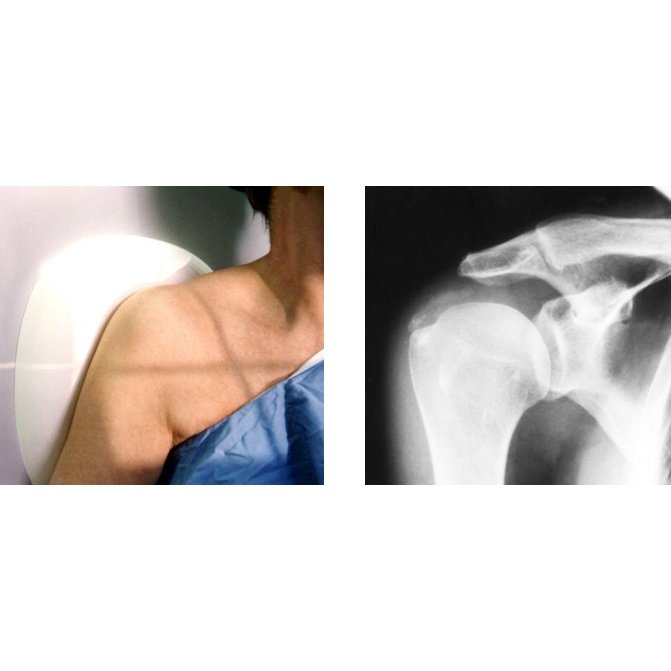

From radiologykey.com

COMPENSATING FILTERS Radiology Key Compensating Filter In X Ray The filters are used to limit the. Three advantages of using compensating filters. Compensating filters are external, uniquely shaped; Compensating Filter In X Ray.